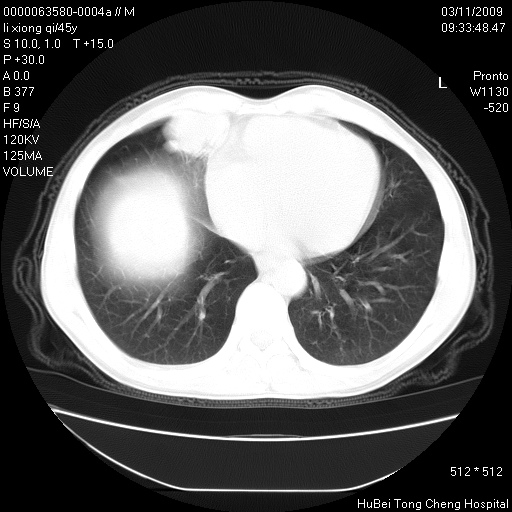

患者 男,45岁。胸痛,咳嗽伴痰中带血1月余。

临床诊断:肺结核?

胸部ct轴位平扫(层厚10mm,螺距1.5,重建间隔10mm),图像如下:

考虑肝癌肺转移

考虑肝癌肺转移。

肝癌肺转移